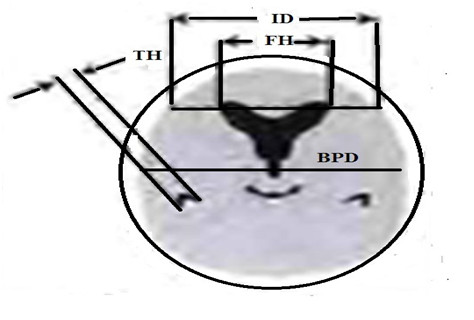

Tiêu chuẩn chẩn đoán xác định dãn não thất (Handbook of Neurosurgery):

- Kích thước sừng thái dương > 2mm + các rãnh Sylvius, rãnh cuộn não bị xóa mờ.

- Kích thước sừng thái dương > 2mm + FH/ID > 0,5

| Tiêu chuẩn gợi ý: - Hình quả bóng NT III và sừng trán NT 2 bên (hình tai chuột Mickey) - Thấm dịch ra tổ chức xung quanh NT - Chỉ số Evan FH/BPD > 0,3 - MRI mặt cắt đứng dọc giữa có thể thấy thể chai bị đẩy lên |